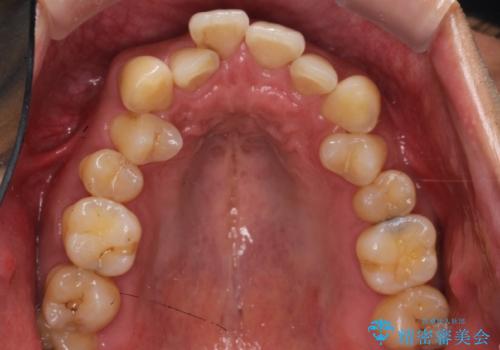

- 前歯のデコボコ(叢生)と、上下の歯の重なりが深い「ディープバイト(過蓋咬合)」を主訴にご来院されました。精密検査の結果、歯が並ぶスペースが不足しているため、上顎左右の小臼歯を抜歯することでスペースを確保し、全体の咬み合わせを改善する治療計画を立案しました。これにより、見た目の改善だけでなく、過度な咬み合わせによって生じる歯や顎への負担も軽減することを目指します。

今回の矯正治療では、まず歯が並ぶスペースを確保するため、上顎の小臼歯を抜歯しました。抜歯によってできたスペースを利用して前歯を奥へ移動させ、デコボコを解消。同時に、奥歯の咬み合わせを調整することで、深すぎた咬み合わせであるディープバイトも改善しました。治療の結果、長年気にされていた前歯のデコボコが解消され、理想的な歯並びに。さらに、正しい咬み合わせを獲得したことで、機能的にも安定した美しい口元になりました。